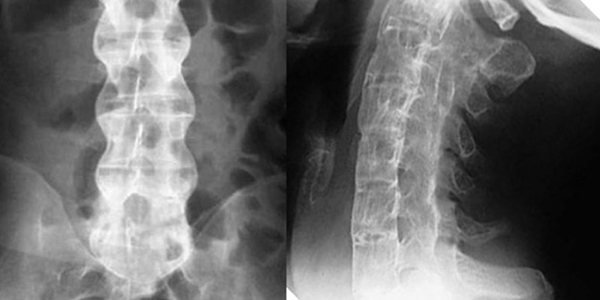

- Chụp X-quang tư thế thẳng và nghiêng để phát hiện các cột sống bị hẹp, hẹp lỗ liên hợp đốt sống, gai xương sống.